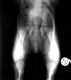

Hund mit HD-Grad B und sehr

lockeren Hüftgelenken in normaler Aufnahmetechnik: keine Luxation |

| Der selbe Hund in der

gehaltenen Aufnahme: Deutliche Subluxation der Femurköpfe. Distraktionsindex 0,50 rechts und 0,47 links |